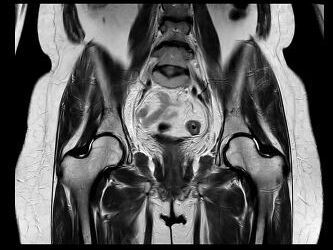

Beispiele von MRT-Becken Aufnahmen